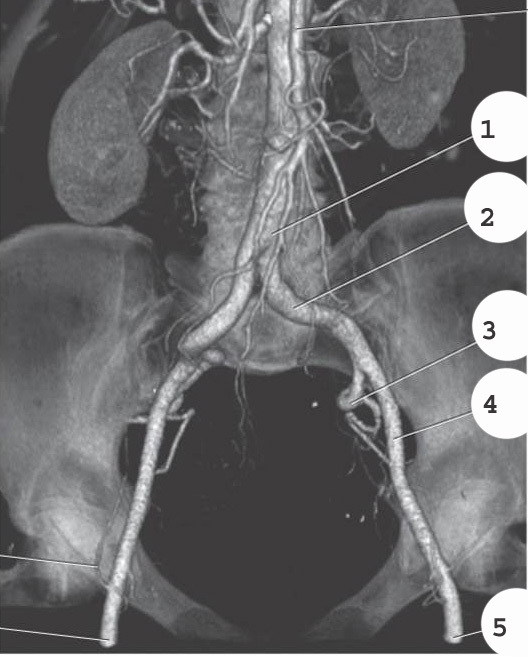

1

Aorta

2

Left common iliac artery

3

Left internal iliac artery

4

left external iliac artery

5

left femoral artery